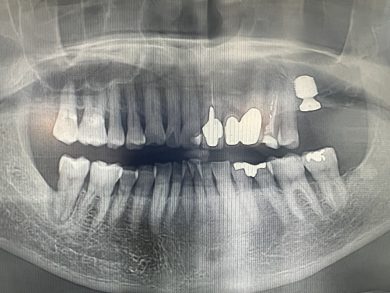

患者さんは75歳の男性。歯性上顎洞炎で公立病院で左上奥歯を抜歯されました。上顎の骨が少なく、公立病院では「インプラントは難しい」と言われた方です。その後当院で義歯を製作しましたが、「やはり自分の歯のように咬みたい」という強いご希望がありました。

診査・診断を重ね、グラフトレスの設計で挑戦することを決断しました。

オペ時間は想定より短く、出血も最小限。術後の痛みも軽度で、患者さんは穏やかな表情でお帰りになりました。そして何より、想定より早期に補綴へ移行できそうです。

その名護先生に本日のレントゲンをお送りしたところ、

「ベスト。経験ある先生ほど臨床をシフトチェンジするのが難しいが、上原先生は見事にシフトチェンジされた」

とお返事をいただきました。